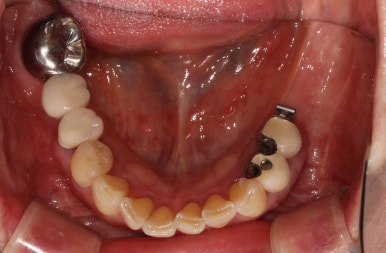

교합면 사진을 보시면, 앞의 두 치아에 surveyed crown (서베이드 크라운)을 설치하고 부분 틀니를 사용하게 하심을 단번에 알 수 있었습니다.

중요한 것은 해당 부위의 대구치 두 개를 뽑은지가 너무 오래되셨고, 틀니를 사용하셔서

대부분의 부착치은 (각화치은)이 사라져 있는 상태였습니다.

왼쪽 아래 어금니의 임플란트 보철물을 모두 만들고 나서의 임상 사진입니다.

자세히 보시면, 맨 뒤 어금니의 바깥쪽으로 단단하게 보이는 부착치은 (각화치은)이 잘 생착되어 있는 것을 보실 수 있어요!!

치료 완료 후 단단한 잇몸과 볼점막의 경계인 MGJ를 화살표로 표시해 보았는데요,

처음 오셨을 때의 사진을 참고해보시면 이해가 편하실거에요.

아무 치료도 하지 않고 브릿지로 치료가 되어있던 부분은 단단한 잇몸이 하나도 없이 대부분 볼점막의 경계를 갖고 있습니다만,